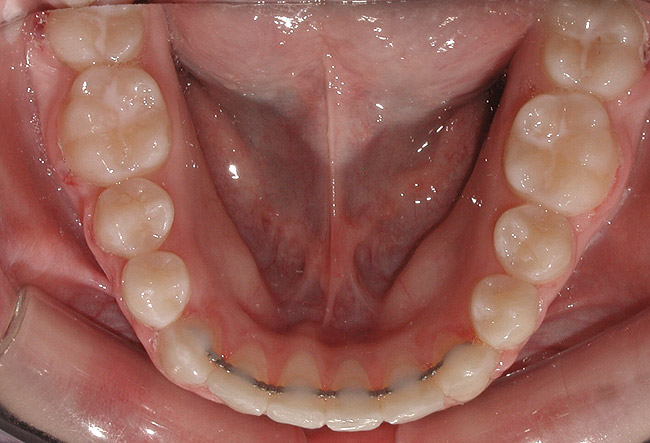

Figure 12 Patient with a bonded retainer on the lower anterior teeth for “lifetime” retention.

Figure 12

Safeguarding the Orthodontic Outcome

Once active orthodontic treatment is successfully completed, it is the responsibility of both the orthodontic and dental teams to help patients safeguard this life-changing investment. It was once believed that after a certain period of time, a properly treated orthodontic result would remain stable for a lifetime. However, based on current knowledge and research, most orthodontists are advocating some sort of lifetime retention for their patients. In patients whose oral hygiene was good during orthodontic treatment, a common method of “lifetime” retention involves the use of “bonded” retainers (Figure 12). In addition, most offices recommend that removable retainers be worn at least two nights per week indefinitely. Most orthodontists continue to follow their patients for a period of between 2 or 3 months to up to 3 years after active treatment is complete. However, it is vitally important that the communication between the dental office and the orthodontic office continue in order to safeguard the orthodontic result. Since orthodontic patients should be returning to their dentist at least every 6 months, the dentist and hygienist should help to encourage them to wear their retainers. In addition, if relapse is noted, it is important that the dental team recommend that these patients return to their orthodontist as soon as possible for an evaluation.